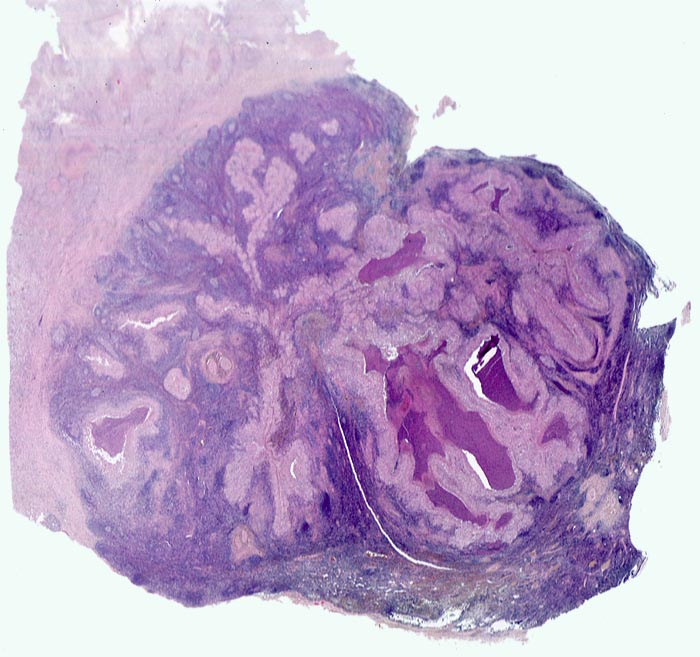

• Girlandenförmige basophile Nekrosezonen durchsetzt von neutrophilen Granulozyten (abszedierende Entzündung).

• Demarkierung der Abszesse durch palisadenförmig angeordnete epitheloide Histiozyten (heller Randwall um die Abszesse).

• Vernarbte verdickte Lymphknotenkapsel.